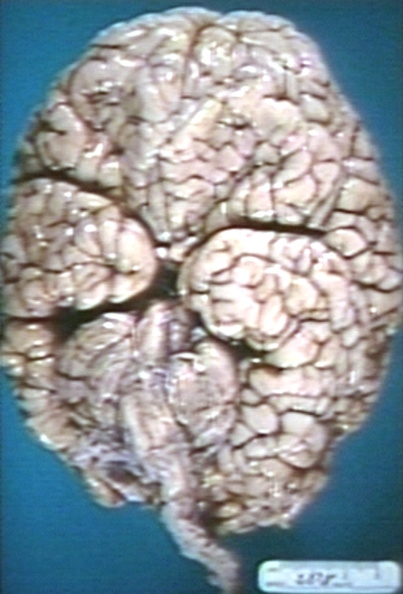

GROSS: NERVOUS: BRAIN: POLYMICROGYRIA, VENTRAL SURFACE OF BRAIN